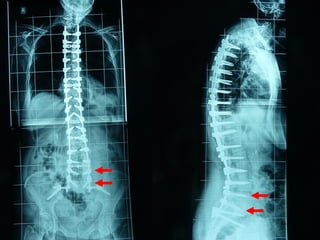

Scoliosis

• Idiopathic adolescent scoliosis

Posterior procedure

Anterior procedure

a. Scoliosis

b. Kyphosis